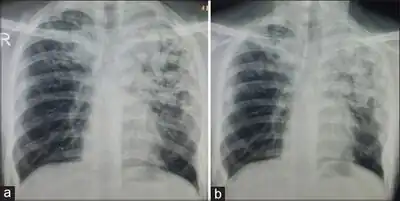

a) Radiograph shows dense radiopacities in the left upper zone which indicate pulmonary tuberculosis b) radiograph after 4 months of treatment shows some improvement